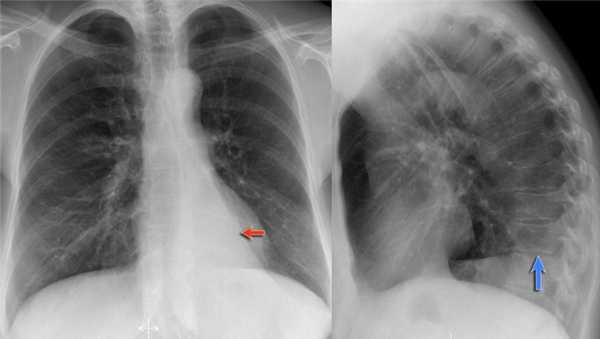

Ателектаз нижней доли левого легкого

На рентгенограмме визуализируются изменения трехгранной формы высокой плотности, расположенные позади тени сердца, что хорошо выявляется на боковом снимке. На боковом снимке при оценке контура диафрагмы спереди назад определяется все менее четко. Исходя из названия раздела напрашивается диагноз — ателектаз нижней доли левого легкого. В норме прозрачность легкого внизу выше, а в нашем случае наоборот (синяя стрелка).

На рентгенограмме органов грудной клетки определяется тотальный ателектаз правого легкого со смещением средостения вправо. На втором снимке представлен тот же пациент, но после лечения. Легкое воздушное и положение средостения в норме. Распространенной причиной тотального ателектаза является неправильно установленная вентиляционная трубка, которая расположена слишком низко и тем самым обтурирует главный бронх.

На ниже представленном снимке представлен пациент с тяжелой бронхопневмонией и тотальным ателектазом. Причиной ателектаза явилось обтурация бронха слизью. После отсасывания мокроты аэрация левого легкого была восстановлена.